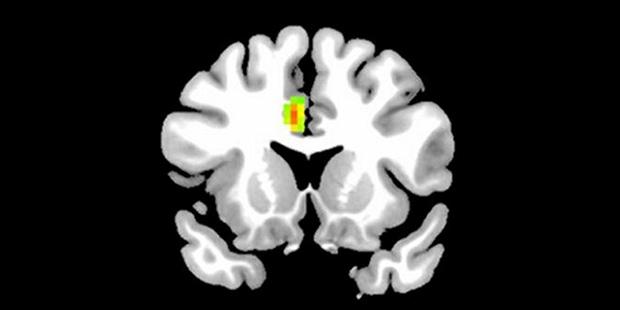

Aşık insanların beyin MR'ı çekildi(Aşık olmayan bir insanın beyni)

MR görüntülerine göre aşık olduğumuzda korku kontrolü, muhakeme, negatif duyguları kontrol etme ve empati gibi yeteneklerimizi geçici olarak kaybediyoruz. Beyin dalgaları üzerinde yapılan araştırmaya göre tutkunu olduğumuz birine baktığımızda değerlendirme yapabilme yeteneğimizi geçici olarak kaybediyoruz.